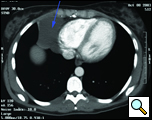

患者は29歳の女性で、喘息のワークアップ中に17歳のときに心膜嚢胞と診断されました。 最近、患者は持続的な咳を呈し、繰り返しCTスキャンで嚢胞の大きさが約6x6cmに増加していることが明らかになった(図1および図2)。 彼女の過去の病歴はWolff-Parkinson-White症候群に対して有意であった。 検査では異常は認められなかった。 嚢胞は拡大しており,有意な不安を引き起こし,持続性咳嗽に寄与している可能性があるため,切除を推奨した。 彼女の心臓専門医は、彼女のWPW症候群は手術に対する禁忌ではないと感じた。

| 図1. 術前の胸部x線。 | 図2。 胸部CTで右心腎性心膜嚢胞を認めた。 |